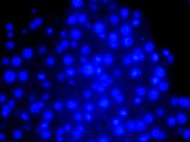

The Human Bone Marrow-Derived mononuclear cells are a mixed population of precursor cells with a single nucleus. The fraction includes monocytes, lymphocytes, as well as hematopoietic stem and...